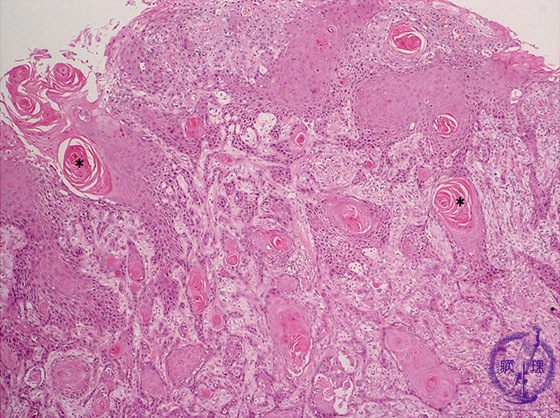

Microscopic finding (HE stain, low-power view): Squamous cell carcinoma nests infiltrate from the surface to the deep margin of the specimen. Tumor nests contain keratin pearls (*).